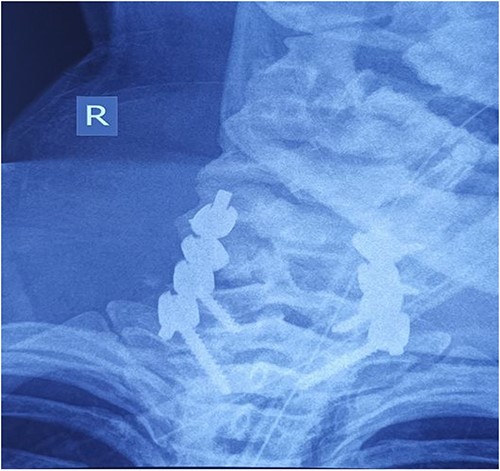

On the fourth day after the injury, the patient was conscious, on low doses of vasopressor support. What was surprising was that in her conscious state she had weakened abduction of the left shoulder, while the right arm and legs were completely plegic (ASIA A). We decided to perform posterior reduction and stabilization from the level of C5 to T1 (Figs 3–5). On the first postoperative day, a follow-up X-ray of the cervical spine was performed (Figs 6 and 7).

Intraoperative finding after repositioning and stabilization: screws placed into the C5-C7 massae laterales and the T1 pedicles; fixation performed with titanium rods.

Cervical spine X-ray postoperatively – AP view: properly positioned osteosynthesis material.

Cervical spine X-ray postoperatively – lateral view: properly positioned osteosynthesis material.